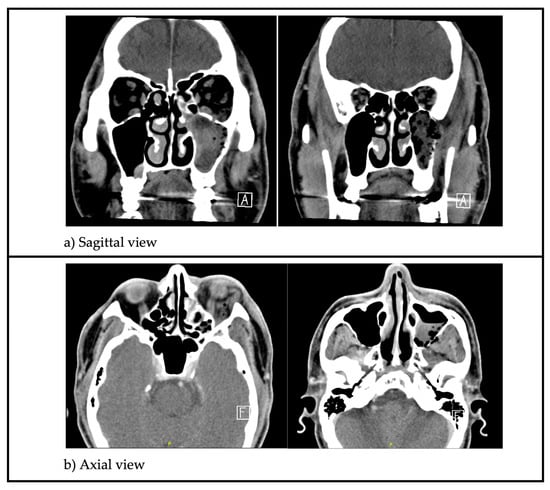

Leukocyte count and C-reactive protein were elevated. A Computed Tomography (CT) scan of the paranasal sinuses (Figure 1) showed opacification with gas pockets within the left maxillary sinus with extensive bony erosion of the sinus walls.

Figure 1.

(a) Sagittal CT images showing opacification of the left maxillary sinus with gas pockets within it. There is significant bony erosion of the sinus walls; (b) Axial CT images highlighting soft tissue gas and inflammation extending beyond the left maxillary sinus to involve the orbit superiorly, infratemporal fossa laterally and subcutaneous tissue of the cheek anteriorly.

Soft tissue inflammation extended beyond the sinus to involve the orbit superiorly (Figure 2), infratemporal fossa laterally and subcutaneous tissue of the cheek anteriorly. The roots of the second and third maxillary molars were seen protruding into the maxillary sinus (Figure 3).